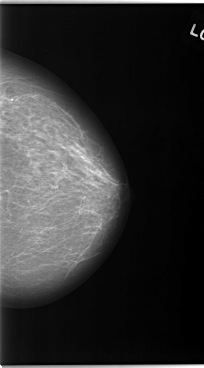

C_0046_1.LEFT_MLO

LEFT_MLO LINES 5824 PIXELS_PER_LINE 3456 BITS_PER_PIXEL 12 RESOLUTION 50 OVERLAY

FILE: C_0046_1.LEFT_MLO.OVERLAY

TOTAL_ABNORMALITIES 1

ABNORMALITY 1

LESION_TYPE MASS SHAPE LOBULATED MARGINS SPICULATED

ASSESSMENT 5

SUBTLETY 5

PATHOLOGY MALIGNANT

TOTAL_OUTLINES 1